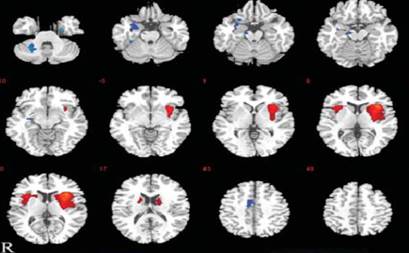

C Luo, Q Li, Y Xia, X Lei, K Xue, Z Yao, Y Lai, W Liao, D Zhou, PA Valdes Sosa, QY Gong, D Yao. Resting state basal ganglia network in idiopathic generalized epilepsy.Human brain mapping 33 (6), 1279-1294,2012

Basal ganglia may have an important role in modulating generalized epilepsy(Luo etal, HBM, 2012)